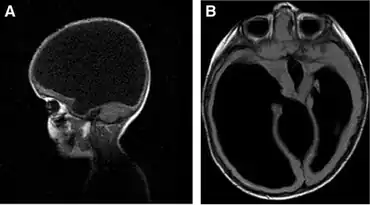

Hydranencephaly is a condition in which the cerebral hemispheres are missing and instead filled with sacs of cerebrospinal fluid. People are born with hydranencephaly, but most of the time, the symptoms appear in a later stage. Newborns with hydrancephaly can swallow, cry, sleep and their head is in proportion to their body. However, after a few weeks, the infants develop increased muscle tone and irritability. After a few months, the brain start to fill with cerebrospinal fluid (hydrocephalus). This has several consequences. Infants start to develop problems with seeing, hearing, growing, and learning. The missing parts of the brain and the amount of cerebrospinal fluid can also lead to seizures, spasm, problems with regulating their body temperature, and breathing and digestion problems. Besides problems in the brain, hydranencephaly can also be seen on the outside of the body. Hydrocephalus leads to more cerebrospinal fluid in the brain, which can result in an enlarged head.[9][10][11]

The cause of hydranencephaly is not clear. Hydranencephaly is a result of an injury of the nervous system or an abnormal development of the nervous system. The neural tube closes in the 6th week of the pregnancy,[12] so hydranencephaly develops during these weeks of the pregnancy. The cause of these injuries/development is not clear.